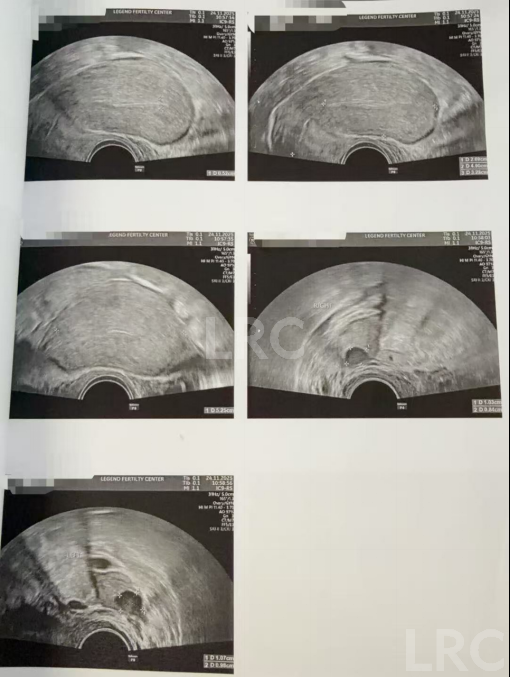

月经第二天 促排第一天

阴超检查:基础卵泡 6 颗

-右侧 3 颗 (4,3,3mm)

-左侧 3 颗 (5,4,3mm)

促排第四天

阴超检查(只数能用卵子):

- 右侧可用卵泡 1 颗(9mm)

- 左侧可用卵泡 1 颗 (10mm)

促排第六天

阴超检查:

- 右侧卵泡 1 颗可用 (11,6mm)

- 左侧卵泡 1 颗 (13mm)

促排第九天

- 右侧卵泡 1 颗可用 (17,8,8,7,5mm)

- 左侧卵泡 1 颗 (19mm)